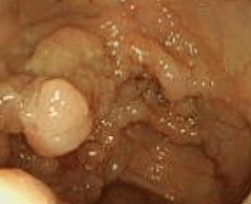

대장내시경 검사는 3일 전부터 음식조절이 필요하며 전날은 5시까지 음식을 섭취할 수 있습니다 5시 이후에는 물만 섭취 가능하며 7시부터 장정결제인 쿨프렙산을 복용합니다 보통 7시에 쿨프렙산을 복용하고 물을 계속 마셔주는데요 복용 후 한 시간 정도 지나면 신호가 오기 시작합니다 그 뒤부터는 물만 마시면 계속 장이 비워지며 새벽 5시에 한번 더 쿨프렙산을 마셔줍니다 그 후 1리터 정도 물을 더 마셔주고 대장내시경 당일 아침 7시에는 가소콜이라는 가스제거제를 섭취합니다 그리고 병원에 내원하셔서 대장내시경을 받으시면 됩니다

수면으로 하게 되면 위와 대장내시경 둘 다 하시는 걸 추천드리는데요 수면으로 하기 때문에 통증이 없으며 눈을 감았다 뜨면 검사가 끝나있습니다 저는 개인적으로 건강검진 센터보다 일반병원이 검사 후 결과를 더 친절하고 자세하게 알려주는 것 같았습니다 검사 후 특별한 이상이 없으면 한 끼만 죽을 드시고 그 후에는 드시고 싶은 걸 드셔도 무방하다고 합니다 40세가 넘어가면 대장내시경을 꼭 받아보는 것이 좋으며 가족 중 대장이나 위에 질환이 있다면 30대부터 한 번씩 체크해 보시는 걸 추천합니다